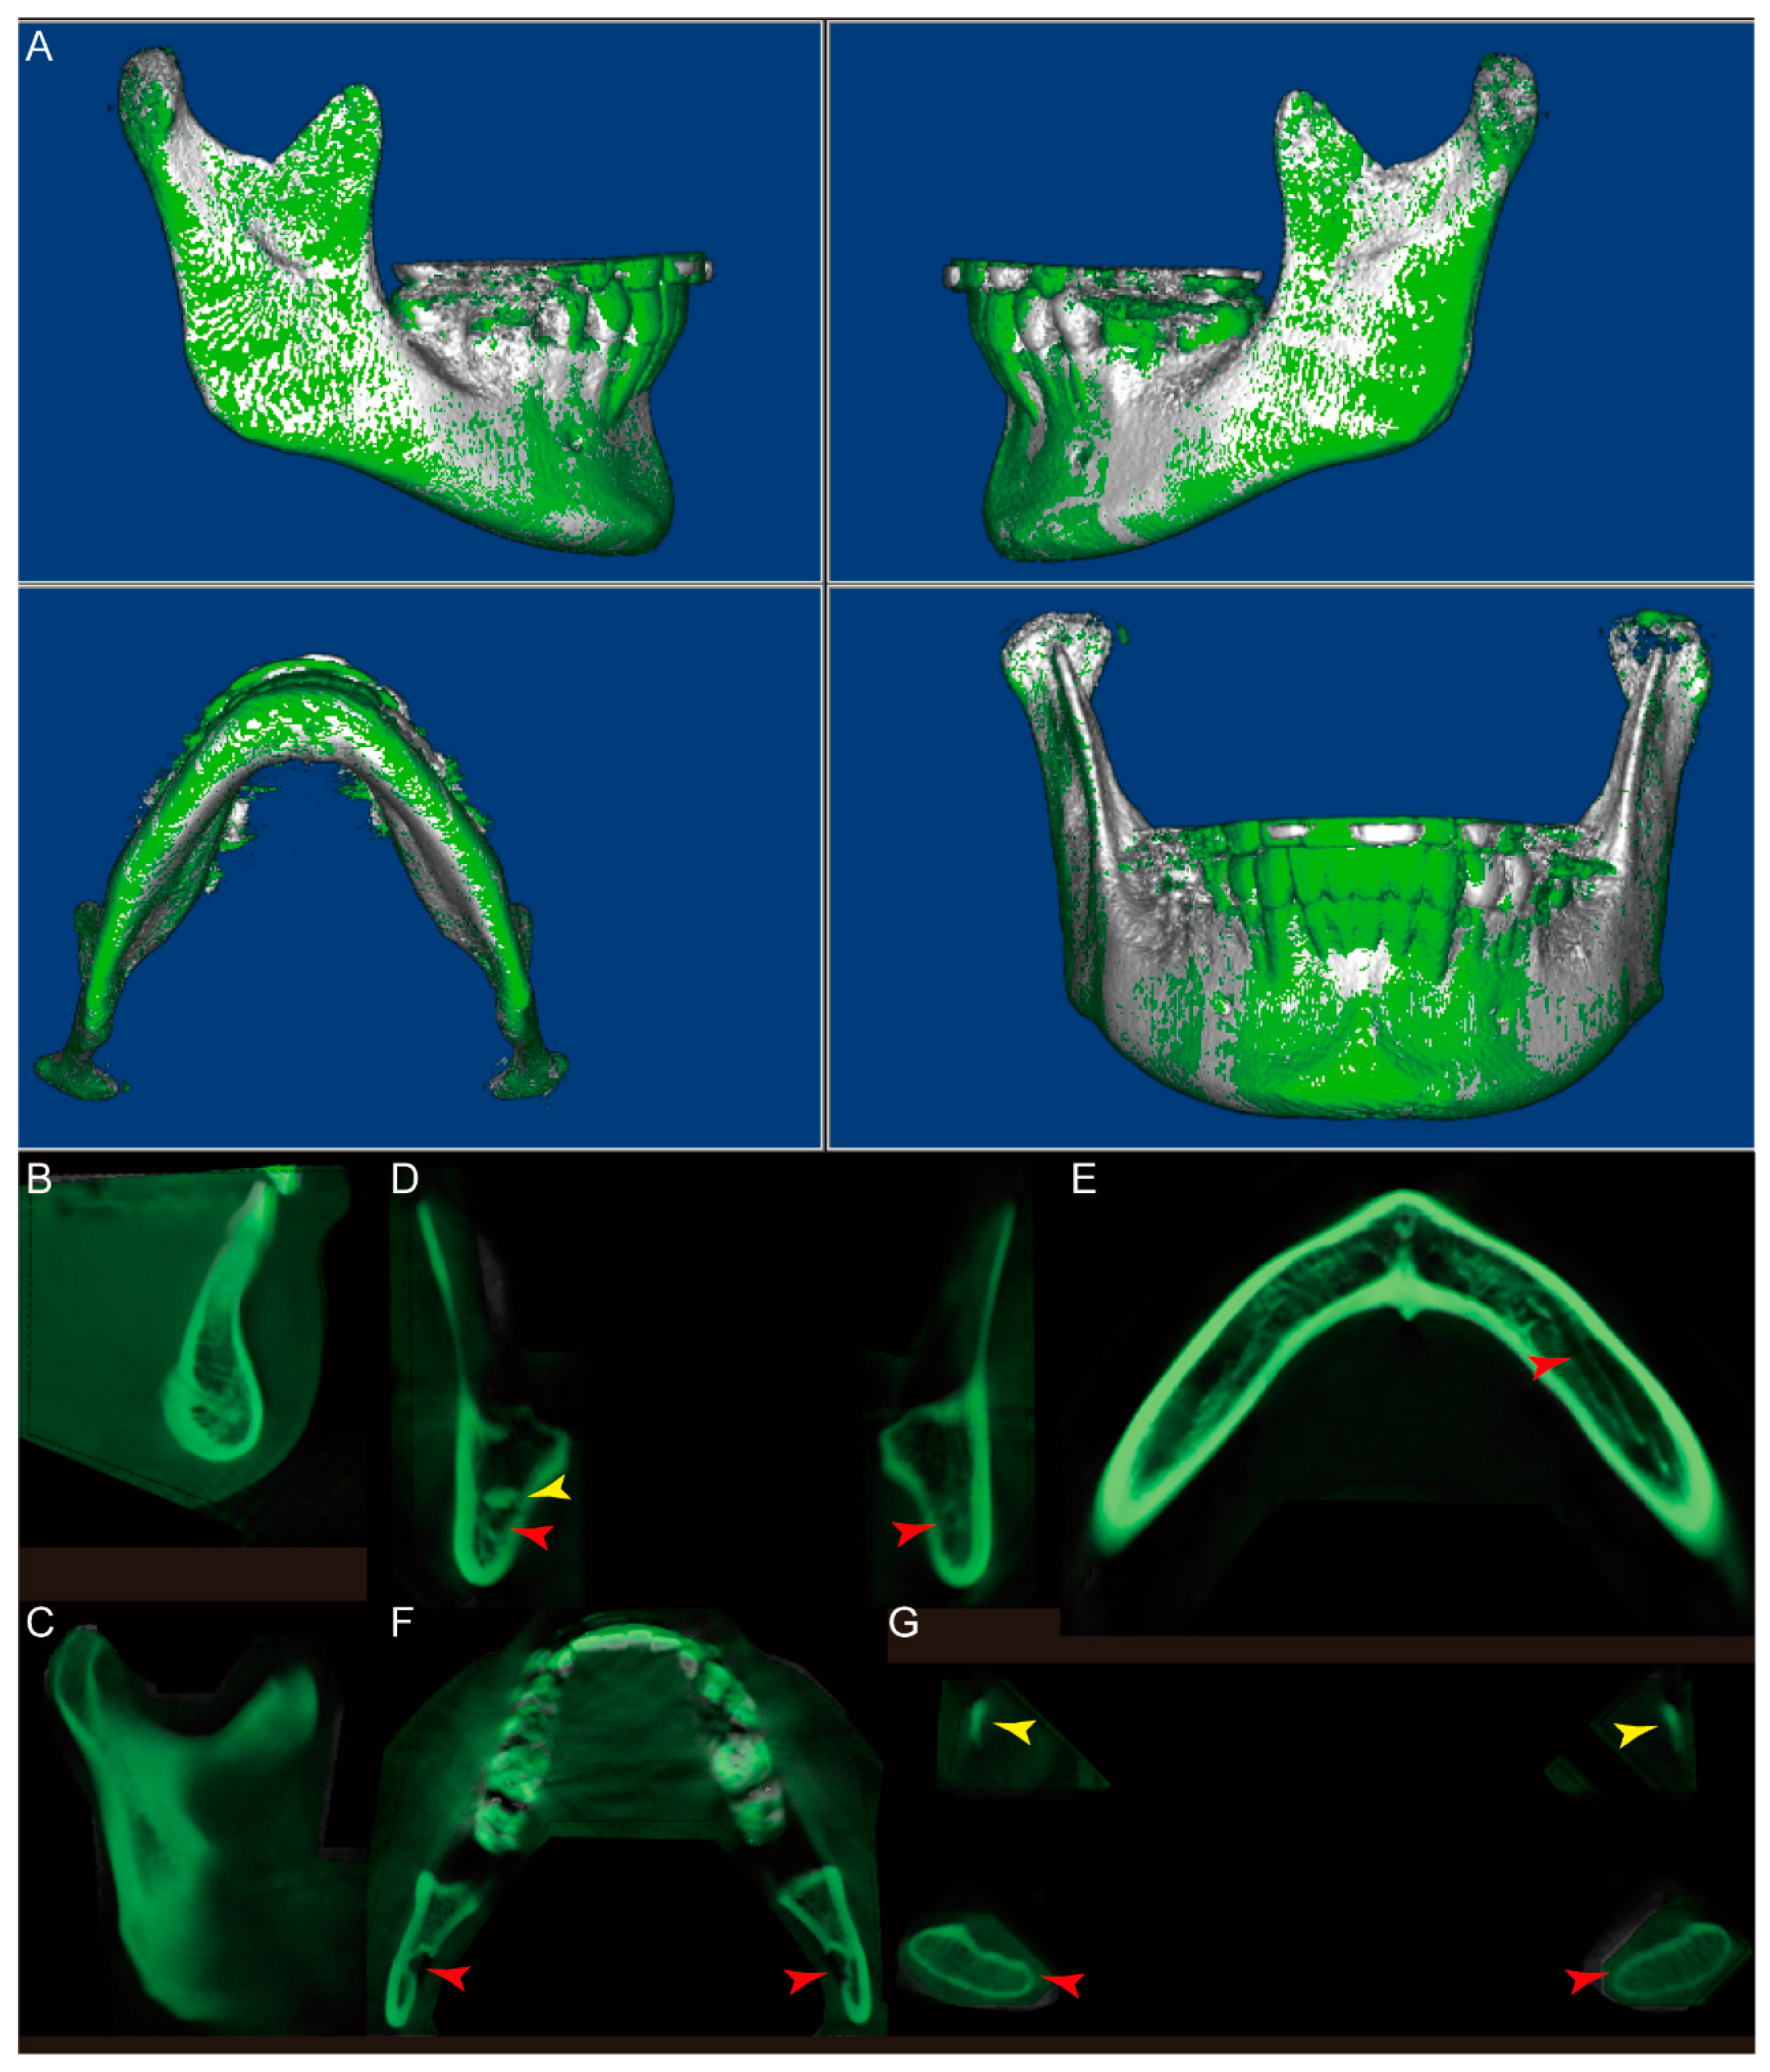

- In the “Sculpting tool” module, orient the CBCT to the right view, and sculpt the majority of the cranial and maxilla structures with the option “free form”, as shown in Figure 1A,B.

- Orient the CBCT to the bottom view in which the borders of the condyles are clearly visible. Sculpt the visible cranial and maxillary structures, as shown in Figure 1C,D.

- Orient the CBCT to the right oblique view (Figure 1E), enlarge the CBCT, and change the “Seg Volumes” to identify the lower and upper density values in the appropriate range to differentiate the condyle from the surrounding structures (Figure 1F). This adjustment will produce a translucent view of the right condyle (orange arrow), glenoid fossa (yellow arrow), and remaining maxillary structures (Figure 1G). Sculpt the glenoid fossa along the inferior border and remaining maxillary structures.